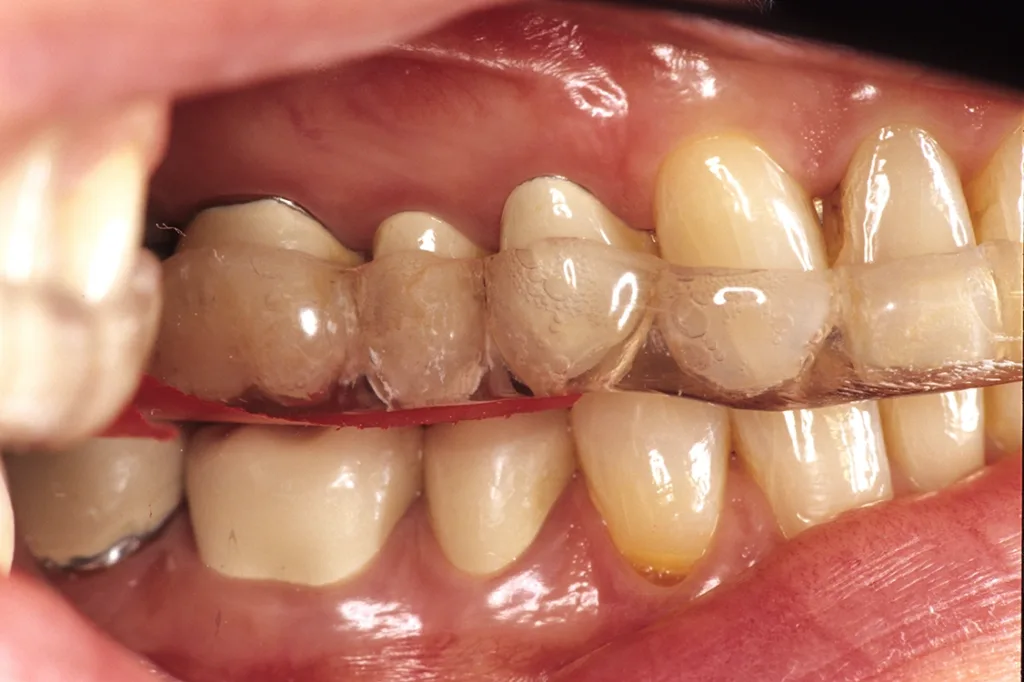

- Anfertigung einer Relaxierungsschiene im OK (bei Deck- oder Tiefbiss im UK) zur funktionellen Dekompensation mit frontalem Aufbiss und temporärer Entlastung im Molarenbereich durch vertikale Freistellung von 1 mm (GOZ 7000 ff.) (Abb. 5 bis 7).

Ziel ist die Dekompensation gewohnheitsbedingter Fehlfunktionen zur Entlastung, Revaskularisierung und Mineralisation des Alveolarknochens vor Implantation. Nach Durchführung der genannten Maßnahmen erfolgt bereits nach einer Tragezeit von vier bis sechs Wochen eine Entlastung von habituellen Gebrauchsmustern. Aus Hygiene- und Stabilitätsgründen werden die Schienen als Streuschienen in einer Stärke von ca. 1,5 mm gefertigt. Sie reichen jeweils bis zum Sechsjahrmolaren (Abb. 8).